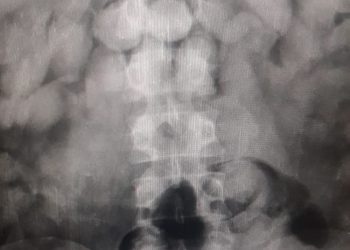

Os quatro homens presos em Belém suspeitos de traficarem droga dentro do corpo foram liberados do hospital nesta quinta-feira (23) após ...